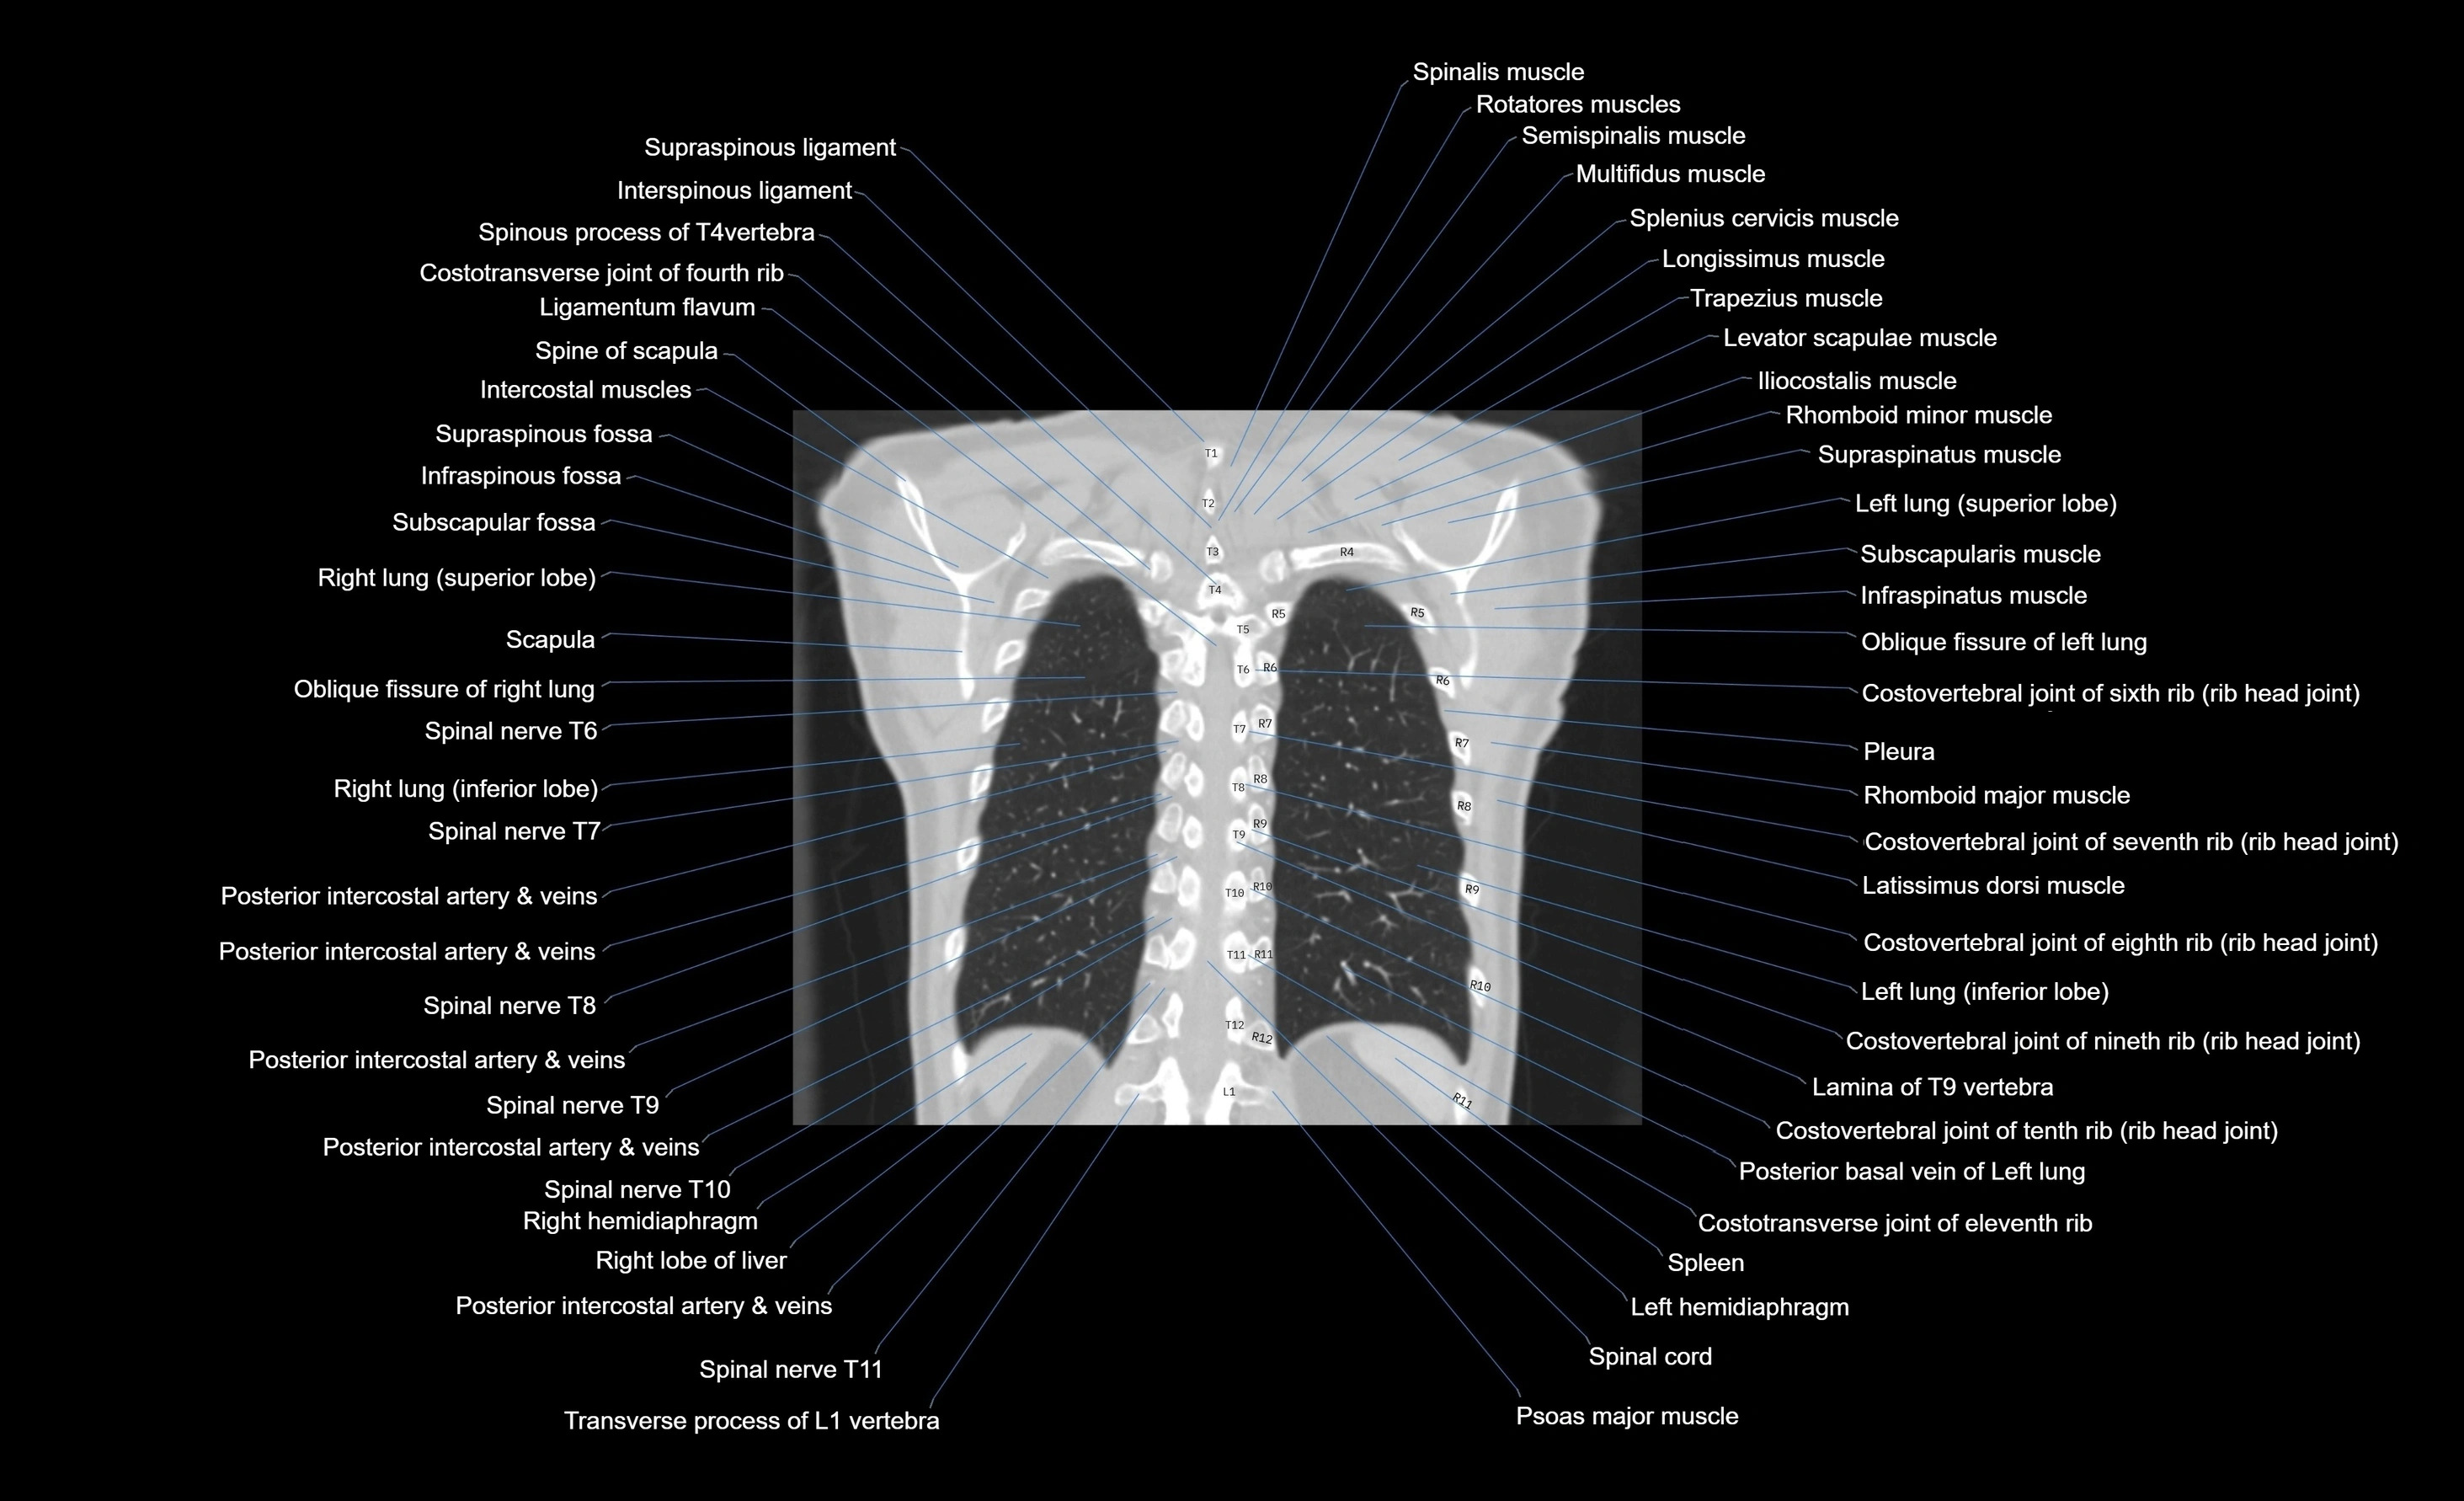

CT images